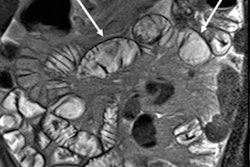

Assessment of small bowel motility using MRI can be of particular value, he continued. Usually it is vital to distend the bowel, as is done for MR enterography, e.g., with 1 L of 2% to 3% mannitol. If a detailed physiological study is being conducted, it is necessary to control the time of day, smoking, caffeine intake, medication, etc. Basic anatomical data are required to plan motility, and the aim is to cover most of the small bowel volume, using a typical slice thickness of 1 cm, breath-hold acquisition at each slice position, and 10 to 25 slice positions to cover the whole small bowel.

Motility information can shed light on conditions such as diabetic neuropathy, pseudo-obstruction, Parkinson's disease, postsurgical ileus, autonomic failure, bacterial overgrowth, and Crohn's disease. However, among the remaining technical challenges are the need for more rapid whole-volume small bowel data acquisition, errors due to through plane motion of loops, automated region-of-interest (ROI) placement, free breathing, tagging, and the requirement for improved registration techniques.